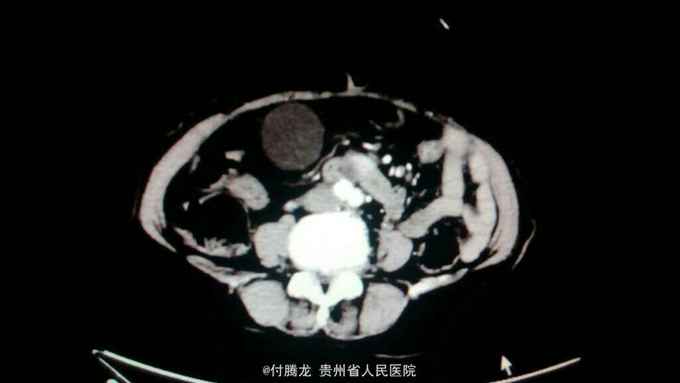

全身黄染伴乏力2月 病史:患者2月前无明显诱因下出现乏力,无恶心呕吐,畏寒发热等,后逐渐发现全身皮肤黄染。遂至当地医院检查。腹部ct提示胆总管下段狭窄,不排除炎性狭窄。胆红素200+。为进一步治疗来我院。

查体:全身皮肤及巩膜重度黄染,上腹轻压痛。 辅助检查:胆红素234,直接胆红素106,间接胆红素128。ALT60,AST88。肿瘤指标199及AFP正常。腹部ct提示胆总管肠内段高密度结节,不排除结石。超声內镜提示胆总管下段梗阻,考虑壶腹部肿瘤。MRCP提示十二指肠壁内段梗阻。